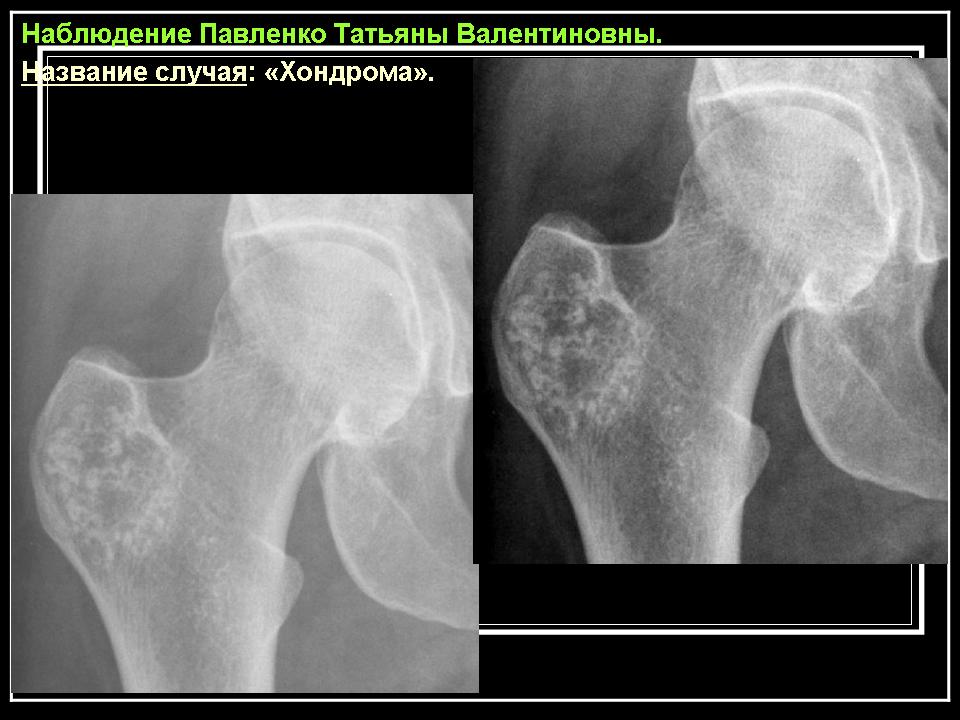

Хондромы являются по морфологическому строению истинными опухолями. Они обладают свойствами присущими опухолям - способностью к прогрессивному росту, рецидивируют. Признаются доброкачественными опухолями, т. к. не метастазируют в отдаленные органы, растут чрезвычайно медленно, нередко годами и даже десятилетиями, заметно не увеличиваясь в размерах. Хотя нет морфологических критериев, которые давали бы основание отличать хондрому одной локализации от другой, локализация в пределах скелета сказывается весьма существенно на клиническом течении хондром. Так, если хондромы коротких трубчатых костей, особенно фаланг кисти не озлокачествляются или озлокачествляются настолько редко, что такие наблюдения описываются как казуистические, то хондромы таза, лопатки, грудины, проксимального отдела бедренной или плечевой костей, озлокачествляются весьма часто. Поэтому больных с хондромами этих локализаций необходимо оперировать также радикально, как и больных с хондросаркомами. Морфологически отдифференцировать хондрому от хондросаркомы высокой степени зрелости нередко затруднительно даже для морфологов высокой квалификации, специально изучающих костную патологию. Подозрение на озлокачествление такого образования может вызвать только четко выраженный рост опухоли, разрушающий окружающую ткань, что наблюдается чрезвычайно редко.

Хондромы не всегда имеют четкие границы с окружающей костной тканью. При распространении за пределы кости они отграничены от окружающих мягких тканей тонкой скорлупой, которая местами может не определяться, но обязательно выявляется у основания кортикального слоя. Могут быть обнаружены вкрапления извести. Окружающая хондрому кость несколько уплотнена, на фоне очага видны известковые включения.

Рентгенологическая картина хондромы представляет четко очерченный опухолевый узел. Очаги минерализации в хондромах выглядят достаточно характерно и представлены очаговыми, глыбчатыми или кольцевидными , арочными отложениями извести. Полного разрушения кортикального слоя трубчатой кости с выходом опухолевых масс в мягкие ткани не наблюдается.